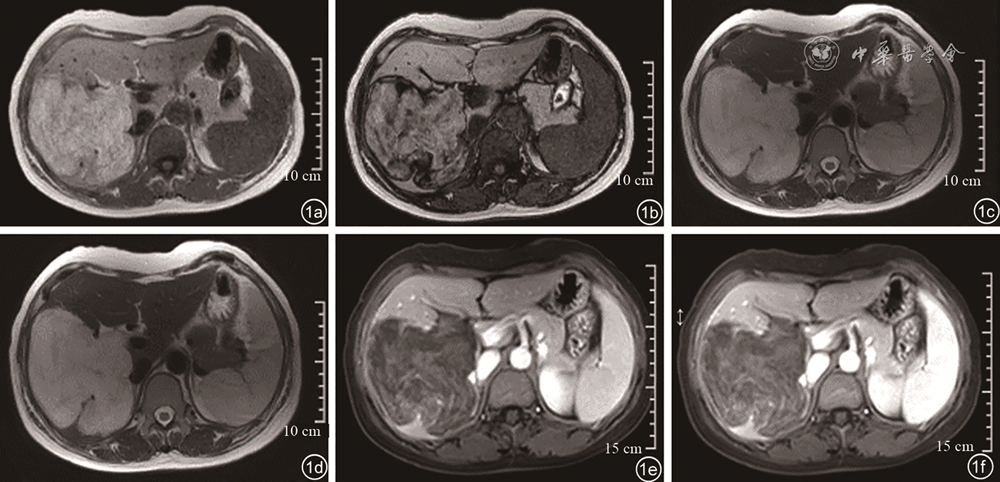

图3 肝右叶高回声肿块超声造影图像。图a为超声造影动脉相(17 s)显示病灶整体均匀高增强;图b为超声造影门脉相早期(47 s)显示病灶呈均匀等增强;图c为超声造影门脉相晚期(114 s)显示病灶内造影剂消退呈稍低增强;图d为超声造影延迟相(180 s)显示病灶内造影剂消退呈低增强